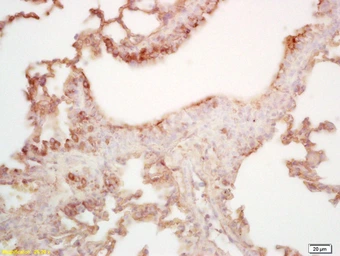

MAL2 antibody

Cat. No. GTX51793

ApplicationsIHC-P

ReactivityMouse